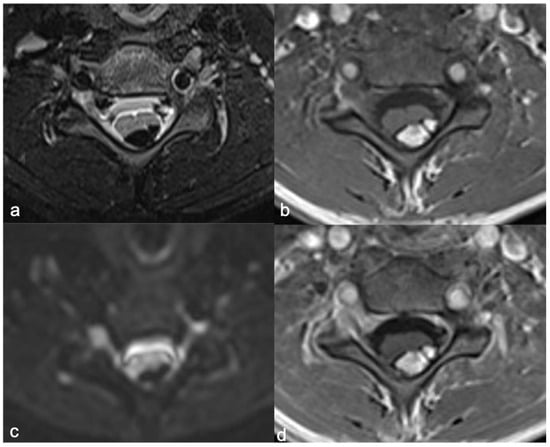

- Rossi, A.; Martinetti, C.; Morana, G.; Severino, M.; Tortora, D. Diagnostic approach to pediatric spine disorders. Magn. Reson. Imaging Clin. N. Am. 2016, 24, 621–644. [Google Scholar] [CrossRef] [PubMed]

- Vargas, M.I.; Delattre, B.M.A.; Boto, J.; Gariani, J.; Dhouib, A.; Fitsiori, A.; Dietemann, J.L. Advanced Magnetic Resonance Imaging (MRI) Techniques of the Spine and Spinal Cord in Children and Adults. Insights Imaging 2018, 9, 549–557. [Google Scholar] [CrossRef]

- Fornasa, F. Diffusion-Weighted magnetic resonance imaging: What makes water run fast or slow? J. Clin. Imaging Sci. 2011, 1, 27. [Google Scholar] [CrossRef] [PubMed]

- Liu, X.; Tian, W.; Chen, H.; LoStracco, T.A.; Zhang, J.; Li, M.Y.; Germin, B.; Wang, H.Z. Advanced neuroimaging in the evaluation of spinal cord tumors and tumor mimics: Diffusion tensor and perfusion-weighted imaging. Semin. Ultrasound CT MRI 2017, 38, 163–175. [Google Scholar] [CrossRef] [PubMed]